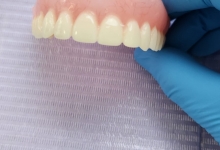

Clinica LUY ESTHETIC ART defineste parodontoza ca fiind rezultatul direct al placii dentare, care se depune pe suprafata dintilor, dar si in apropiere de marginea gingivala. Aceasta boala duce la pierderea dintilor, chiar daca ei sunt aparent sanatosi si nu prezinta carii. Edentatiile, afecteaza vorbirea, aspectul, dar si capacitatea de a mesteca.

Boala parodontala are un caracter progresiv. Pentru cazurile mai grave, recomandam tratamentul parodontal chirurgical rezectiv sau regenerativ.